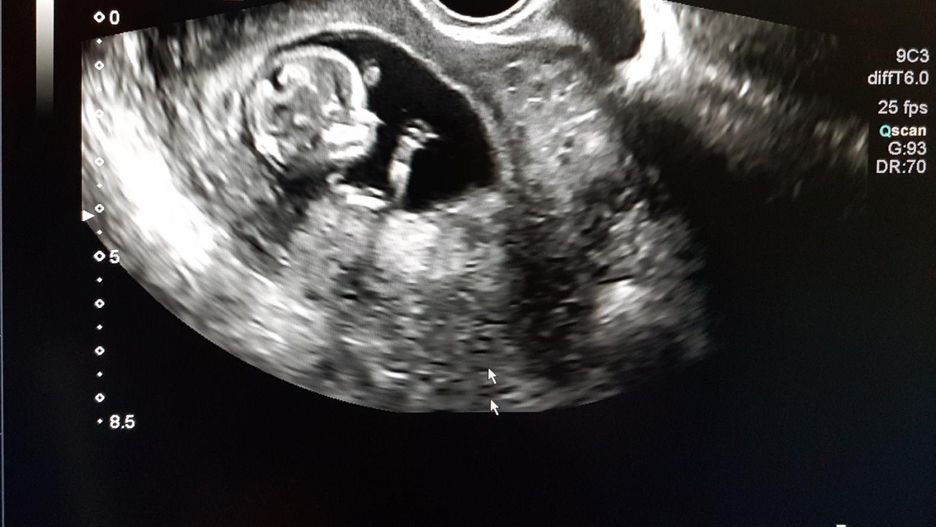

Do szpitala w Bihar (Indie) zgłosili się rodzice z 40-dniowym noworodkiem. Chłopiec miał wzdęty brzuszek i nie był w stanie prawidłowo oddawać moczu. Lekarz dr Tabrez Aziz postanowił więc zlecić tomografię komputerową, by ustalić dokładną przyczynę złego stanu zdrowia maluszka.

Nie spodziewał się jednak, że to, co zobaczy, obiegnie media na całym świecie. Badania wykazały bowiem, że w brzuchu niemowlęcia znajduje się kolejny płód. Maluch został natychmiast przewieziony do specjalistycznego centrum medycznego Motihari na leczenie.

- Podczas badań na jaw rzadka anomalia polegająca na tym, że płód rozwijał się w żołądku 40-dniowego niemowlęcia. Nazywa się to "Fetus in fetu" (płód w płodzie). Niemowlę przeszło operację, jego stan jest stabilny – powiedział dr Aziz.

Do zjawiska jakie określa się mianem "płodu w płodzie", dochodzi wskutek nierównego podziału komórek w ciąży wielopłodowej i wchłonięciem jednego bliźniaka przez drugiego, silniejszego. Podobnie jak w przypadku potworniaka, jest to malformacja, jednak różni się ukształtowaniem masy oraz budową. Znajduje się bowiem w błonie odpowiadającej workowi owodniowemu.

Jak zaznacza dr Aziz, jest to bardzo rzadka anomalia, która zdarza się raz na pół miliona urodzeń. Do tej pory opisano jedynie 200 takich przypadków.